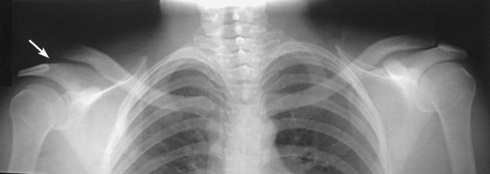

The shoulder girdle is formed by two bones—the clavicle and scapula. The function of these bones is to connect the upper limb to the trunk. Although the alignment of these two bones is considered a girdle, it is incomplete in front and in back. The girdle is completed in front by the sternum, which articulates with the medial end of the clavicle. The scapulae are widely separated in the back. The proximal portion of the humerus is part of the upper limb and not the shoulder girdle proper; however, because the proximal humerus is included in the shoulder joint, its anatomy is considered with that of the shoulder girdle (Figs. 5-1 and 5-2).

The clavicle, classified as a long bone, has a body and two articular extremities (see Fig. 5-1). The clavicle lies in a horizontal oblique plane just above the first rib and forms the anterior part of the shoulder girdle. The lateral aspect is termed the acromial extremity, and it articulates with the acromion process of the scapula. The medial aspect, termed the sternal extremity, articulates with the manubrium of the sternum and the first costal cartilage. The clavicle, which serves as a fulcrum for the movements of the arm, is doubly curved for strength. The curvature is more acute in males than in females.

The scapula, classified as a flat bone, forms the posterior part of the shoulder girdle (Figs. 5-3 and 5-4). Triangular in shape, the scapula has two surfaces, three borders, and three angles. Lying on the superoposterior thorax between the second and seventh ribs, the medial border of the scapula runs parallel with the vertebral column. The body of the bone is arched from top to bottom for greater strength, and its surfaces serve as the attachment sites of numerous muscles. The flat aspect of the bone lies at about a 45- to 60-degree angle in relation to the anatomic position (see Fig. 5-2).